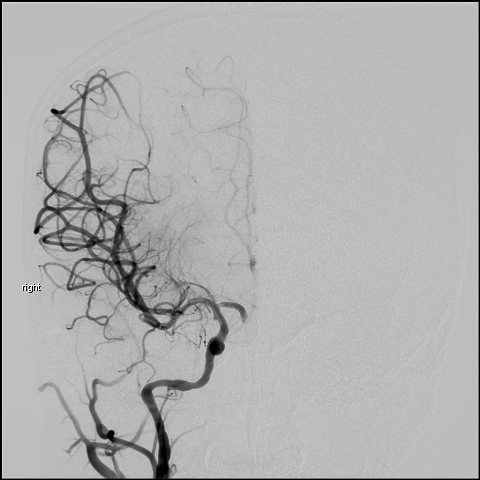

初秋的午后,空气中弥漫着令人烦躁的闷热;在介入科医生办公室内,值班医生正忙着一早上手术后的文书工作;突然,急促电话铃声打破了办公室的宁静;“喂,四爷(四爷是介入科医生对施振静副主任医生的称呼)”;“万松院区有个脑梗,8岁的小姑娘,你马上过来下”这是施振静医生的电话,简短的语句中夹杂着一丝焦急,过了十几秒,值班医生电话铃声再次响起,“这个病人才8岁,血管相对较细,你去把手术室里我们取栓的常规器械带上,然后带上6F 55cm和70cm的长鞘各一个,我这边送手术了”;电话再次挂断;值班医生带上手术器械,马上驱车从瑞祥院区赶往万松院区;原来,这是一个8岁的小姑娘,因“乏力伴面色苍白3天”入院,入院诊断:1.病毒性心肌炎 2.急性上呼吸道感染;今日9:30,患者出现头痛症状,查体双眼右侧凝视,伸舌稍偏左,左侧肢体肌力III级,左侧巴氏征可疑阳性,MRA检查提示脑梗塞(右侧颈内动脉末端栓塞);在麻醉师一系列娴熟的操作下,诱导、麻醉、插管,13:18分,麻醉成功;同时,介入科医生也在紧锣密鼓的在做一系列的术前准备,13:19,施振静医生开始股动脉穿刺,紧接着是置管、造影,造影提示右侧颈内动脉末端栓塞,与术前MRA检查一致,紧接着是经鞘管送人取栓导管、取栓支架,13:44,在紧张又有序中,介入科两位手术医生从患者体内拉长了取栓的导管及支架,“我看到一块暗红色的血栓了”值班医生有点兴奋的说了一句,“我这里血管通了”,这是施振静医生的话,短短的几个字,感觉到了一丝的放松,没有了之前的紧张情绪;就这样,经过紧张又短暂的15分钟,栓塞的血管被我们成功开通了,术后转重症监护室治疗;16:30,患者神志转清,成功气管拔管,术前下降的肌力基本恢复正常;

短短的15分钟,成功开通栓塞血管,这是我院目前为止取栓年龄最小的患者,假设没有我院强大的卒中团队的精密合作,没能在最短的时间内给予开通栓塞血管,没有大家全力与时间赛跑,这个受伤的小天使,有可能就要坠落了,但是,在我们的全力守护下,小天使有了重返健康的希望。